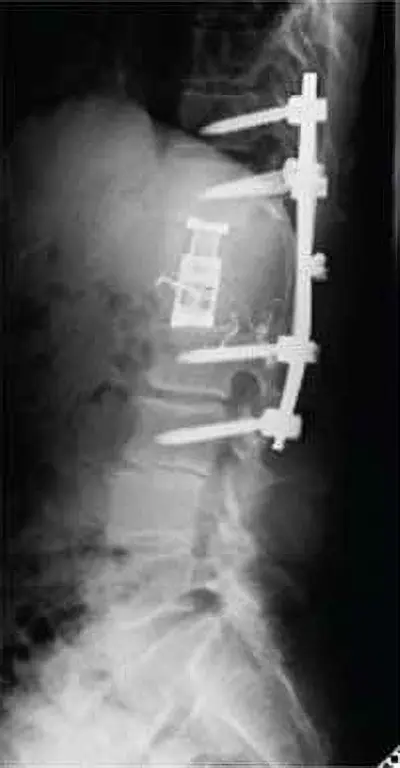

[50代 転移性脊椎腫瘍] 第3腰椎転移性脊椎腫瘍に対して椎弓切除+後方固定施行